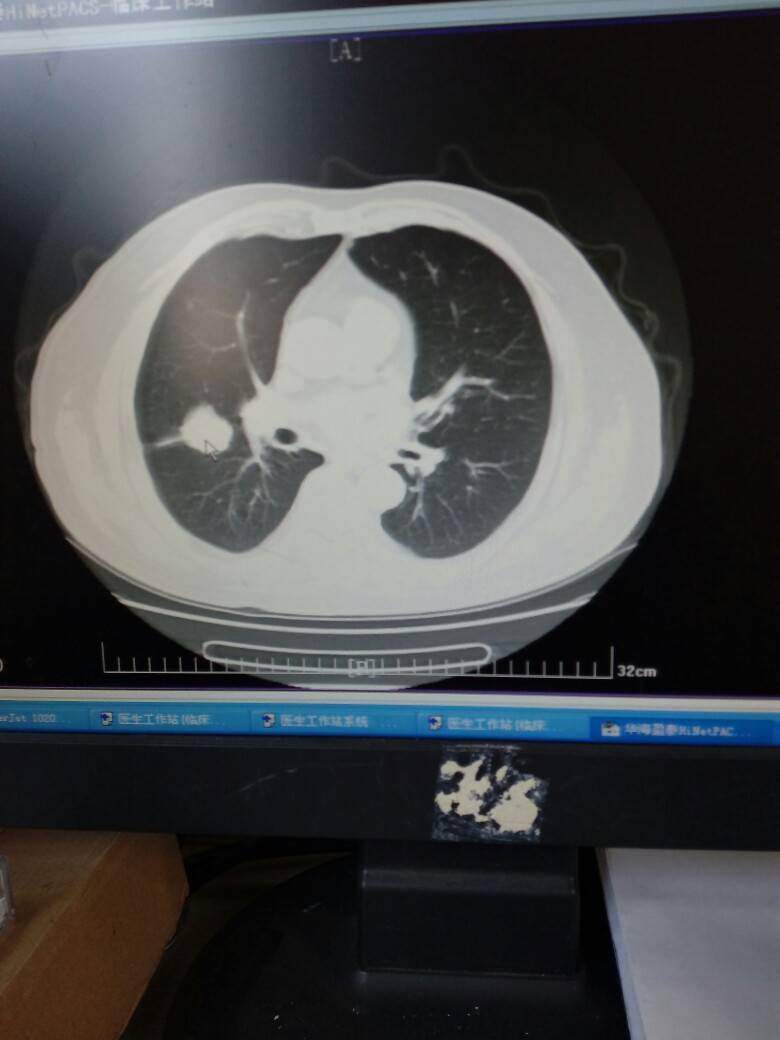

肺鳞癌2个月余,给予gp方案化疗2次,大家看看能否手术,这是最大的肿瘤

术前ct见右上肺肿瘤